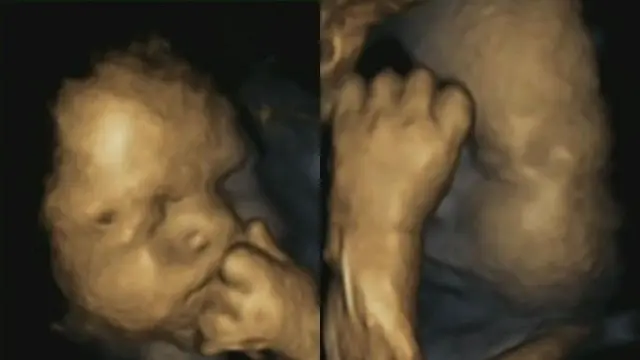

Sebuah penelitian terbaru menunjukkan foto yang membuktikan tentang teori stres pada ibu hamil. Saat ibu hamil mengalami tekanan dan stres, bayinya akan mengalami kecemasan serupa. Karena itulah ibu yang sedang hamil tak boleh terlalu banyak bersedih atau stres karena bayi yang ia kandung juga merasakan hal tersebut.

Foto bayi dari ibu yang sedang tertekan pun diambil lewat mesin scanner 4D. Ditunjukkan bagaimana janin yang masih ada dalam kandungan itu menyentuh mulut dan keningnya seperti seseorang yang sedang cemas dan gelisah. Ini karena reaksi hormon stres yang dihasilkan oleh ibu.